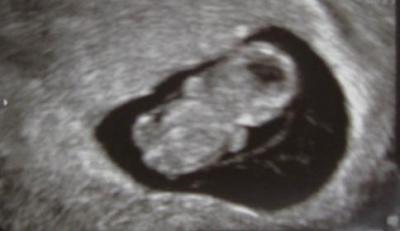

es ist geschafft! der arzttermin verlief super und ich durfte sogar 2 Bilder mitnehmen! :-) Das Kleine ist 2,4 cm groß und Arzt meinte, es ist alles wie es sein soll... Das Herzchen hat wie wild geschlagen und das war so schön zu hören, bin immer noch hin und weg. Mir stiegen gleich die Tränen in die Augen... Am 19.3. habe ich den nächsten Termin mit NFM.

Bild zu mein kleines würmchen... - Forum für September - Mamis

bin 9+2, hatte ich mir auch ausgerechnet... Arzt sagt, das Kleine ist bestens entwickelt für 9+2...

Süß das Bild von deinem Würmchen.... Auf meinem Bild waren wir genau bei 9+2, die Ärztin hatte den Termin etwas zurück gesetzt, weil es ein bissl kleiner war. Aber beim Ultraschall am 17.2. sagte sie von der Größe wäre es jetzt bei 11+2 anstatt bei 10+6. Also gut entwickelt :-)